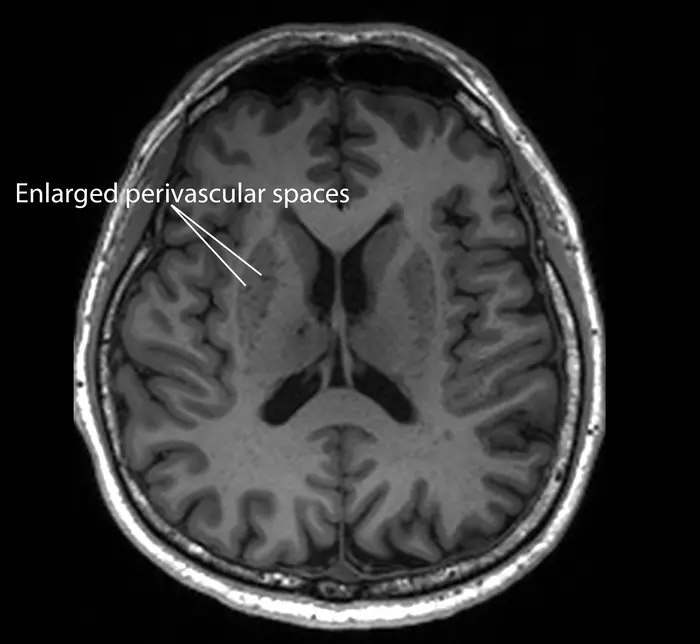

A magnetic resonance imaging image of a patient who has enlarged perivascular spaces, which are seen as dark lesions in dark grey regions around the centre of the brain.